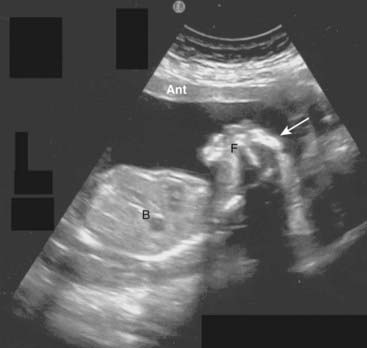

image If a gestational sac (the earliest sonographic finding in pregnancy, appearing at about 4-5 weeks gestational age), yolk sac (first structure to be seen normally in gestational sac), or viable fetus is identified in the uterine cavity, an ectopic pregnancy is effectively excluded. Endovaginal examinations are usually performed to find the gestational sac (Fig. 19-26).

image

Figure 19-26 Early intrauterine pregnancy.

There is a single live intrauterine pregnancy (solid white arrows) contained within the gestational sac (solid black arrow) inside the uterus (U). Using a measurement called the crown-rump length, (between the white arrows) the embryo (E) was estimated at 9 weeks of age. Sonographic gestational age begins on the first day of the last normal menstrual cycle because, for most individuals, that is a more certain date than the actual date of ovulation.

imageWhile it is possible to have simultaneous intrauterine and extrauterine pregnancies, such heterotopic pregnancies are extremely rare, other than in fertility patients, so that identification of an intrauterine pregnancy effectively excludes an ectopic pregnancy.